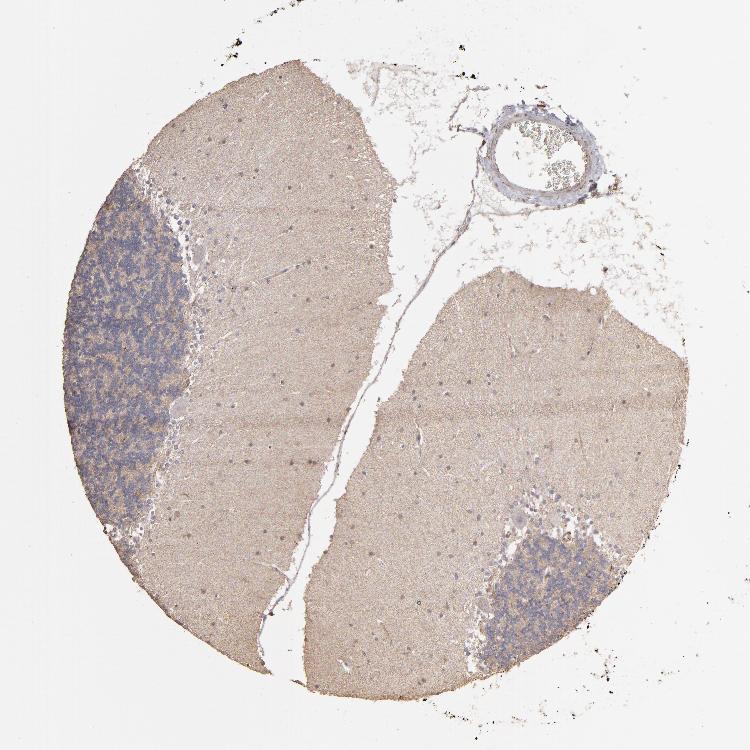

CEREBELLUM - Antibody stainingi

Antibody staining in the annotated cell types in the current human tissue is reported as not detected, low, medium, or high, based on conventional immunohistochemistry profiling in selected tissues. This score is based on the combination of the staining intensity and fraction of stained cells.

Each image is clickable and will lead to virtual microscopy that enables deeper exploration of all samples and also displays staining intensity scores, fraction scores and subcellular localization as well as patient and tissue information for each sample.

Antibody HPA001820Antibody CAB022050

Purkinje cells Not detectedHigh

Cells in granular layer LowHigh

Cells in molecular layer LowHigh